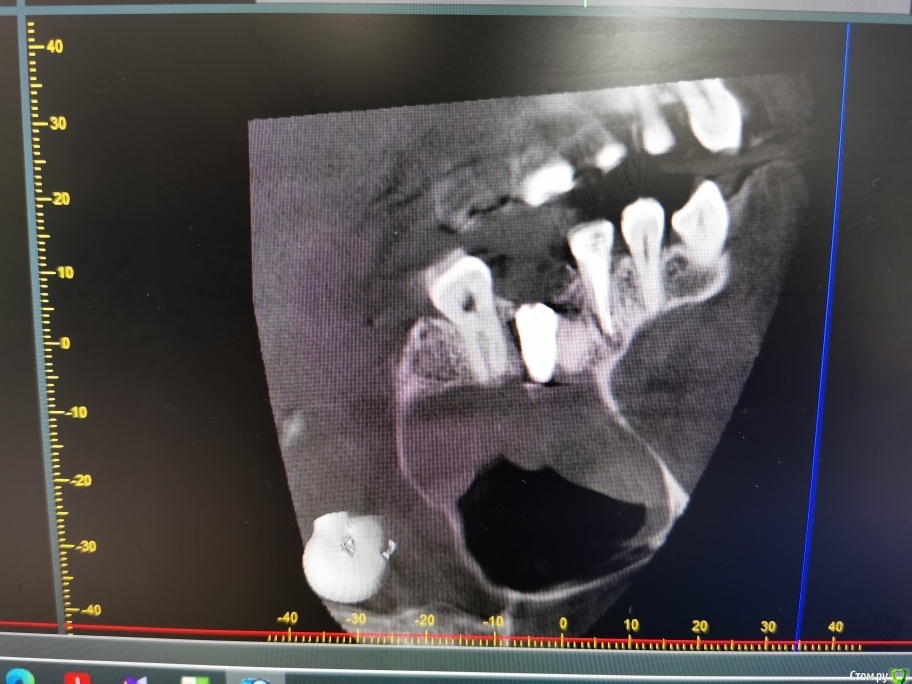

olga.maverick Опубликовано 1 марта, 2021 Поделиться Опубликовано 1 марта, 2021 (изменено) Здравствуйте!Вместо удалённого год назад зуба, 18 февраля врач установил мне в верхнюю челюсть имплант Импро, без синус лифтинга, сказал, что между слизистой и имплантом проложил губку, она рассосётся и кость нарастёт. Он сделал контрольный снимок-рентген, подтвердил, что имплант в пазухе, но под слизистой и это по его мнению норма. Пять дней я пила Амоксиклав по его назначению. Сегодня, первого марта сделала снимок КЛКТ, т.к. не проходит. насморк и дискомфорт в районе пазух.Получилась вот такая картина-сильный отёк в районе правой пазухи , до установки импланта отёка не было, есть снимок, сделанный перед операцией. Помогите пожалуйста разобраться:1) Всё идёт по плану, отёк временная реакция, имплант установлен профессионально или всё плохо?2)Нормально ли, что имплант стоит не посередине, а впритык к одному зубу? Изменено 1 марта, 2021 пользователем olga.maverick Ссылка на комментарий

olga.maverick Опубликовано 1 марта, 2021 Автор Поделиться Опубликовано 1 марта, 2021 (изменено) И, ещё, уважаемые доктора, если позволите вопрос. В левой пазухе у меня отёк уже несколько лет. Один маститый лор сказал, что у меня киста и он мне её удалит. Другой оперирующий лор сказал, что кисты нет, есть пломбировочный материал под слизистой, внутри пазухи ничего нет, кроме отёка слизистой.Мой врач (речь о котором в посте выше) утверждает, что в 27 зубе, максимально близко подходящем к пазухе, нет пломбы, зуб девственный. А я не помню, что и когда лечила. У вас есть версии, что за крапинка на снимке в левой пазухе и кому идти за решением, к лору или стоматологу)? Маюсь хроническим ринитом и периодическими гайморитами. Изменено 1 марта, 2021 пользователем olga.maverick Ссылка на комментарий

olga.maverick Опубликовано 2 марта, 2021 Автор Поделиться Опубликовано 2 марта, 2021 (изменено) А я наоборот загрустил, хотел бы Вас иметь как свою пациентку, грамотная речь, стремление разбираться в технологических нюансах, выдает в Вас образованного, современного человека, отчаянного, но приятного в общении. Но разумеется уже поздно, дело сделано. Хорошо, а если сейчас кто ни будь выразит "компетентное" мнение, что все чудовищно плохо и имплант надо быстро удалить, только тогда сразу пройдет отек, какие будут Ваши действия? Вы послушаете эксперта инкогнито, примите это к действию? Но самое главное и это действительно важно! Как Вы выбрали клинику, по каким критериям?Спасибо за добрые слова.) Разумеется, я не буду руководствоваться вердиктом из интернета, но, аргументированная оценка может добавить понимания. В том то и беда, что врач выбран по средствам, а не по отзывам или особому доверию. Несложный в исполнении имплант он вроде хорошо мне сделал, пол года стоит, я решилась на второй, но чуйка говорит, что я рискнула. Обычно в клиниках обрабатывают клиента психологически: Договор, анализы, паспорт с голограммами имплантов, тщательное изучение снимков, моделирование имплантации в программе, подробные разъяснения. В моём случае ничего этого не было. Беглый взгляд на снимок и без всяких прелюдий, сверло в рот. Это странно и наводит на мысли о кустарщине. Изменено 2 марта, 2021 пользователем olga.maverick Ссылка на комментарий